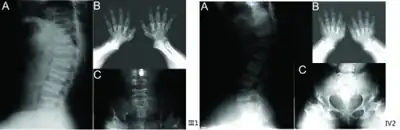

a) Anterior beaking of vertebral bodies b) short metacarpals and phalanges, cone-shaped epiphyses c) scoliosis, small femoral heads, flared metaphyseal borders -